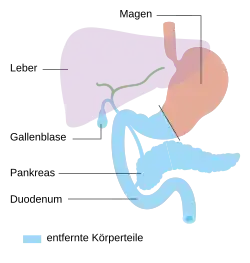

- Operationsvarianten

-

Pylorus-erhaltende Teilresektion

Pylorus-erhaltende Teilresektion -

Duodenopankreatektomie nach Whipple

Duodenopankreatektomie nach Whipple -

Endzustand nach Whipple-Operation

Endzustand nach Whipple-Operation -

Totale Pankreasresektion

Totale Pankreasresektion -

Endzustand nach Totalresektion

Endzustand nach Totalresektion